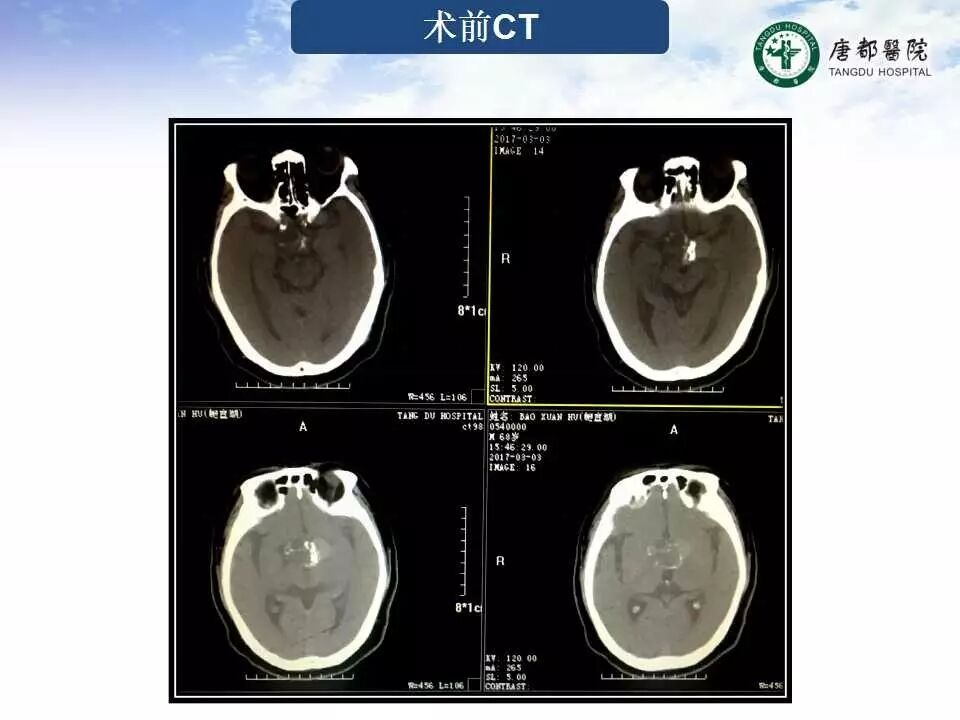

Case 4

长按并识别二维码即可查看该手术视频